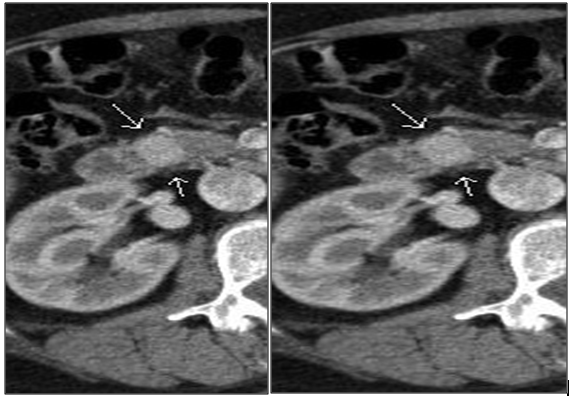

1. Ultrasound and a CT scan with contrast, which showed a single oval nodule with 17x13mm in relation to the duodenal part of the head of the pancreas with rapid clearance of the contrast, unidentifiable in portal phase or late acquisitions (Figure 2A-D).

A/B. Arterial phase. C/D. Early and late portal phase.

Figure 2 Computed tomography with contrast.